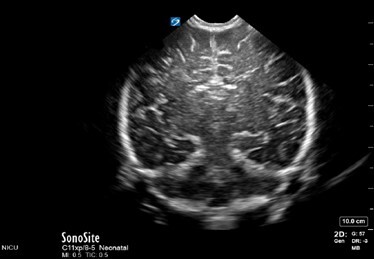

Neonatology Normal Anatomy Far Gain Too Low Image